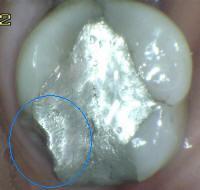

3. CARIES CON EXPOSICIÓN DENTINA

1. CAVIDAD DETECTABLE EXPONIENDO DENTINA

1. ACTIVIDAD

1. activa/inactiva

2. HALLAZGO CLÍNIICO:

1. cavidad en esmalte, con exposición de dentina

2. DIAGNÓSTICO

1. lesión cariosa cavitacional con exposición de dentina

2. TRATAMIENTO

1. operatoria

1. promoción y prevención

2. CRITERIO DE DIAGNOSTICO

1. cavidad detectable con dentina visible esmalte opaco o decolorado exponiendo dentina

1. ICDAS 5

2. CAVIDAD EXTENSA, DENTINA CLARAMENTE EXPUESTA

1. activida/inactiva

2. HALLAZGO CLINICO

1. Cavida extensa

1. ICDAS 6

1. promoción y precvención